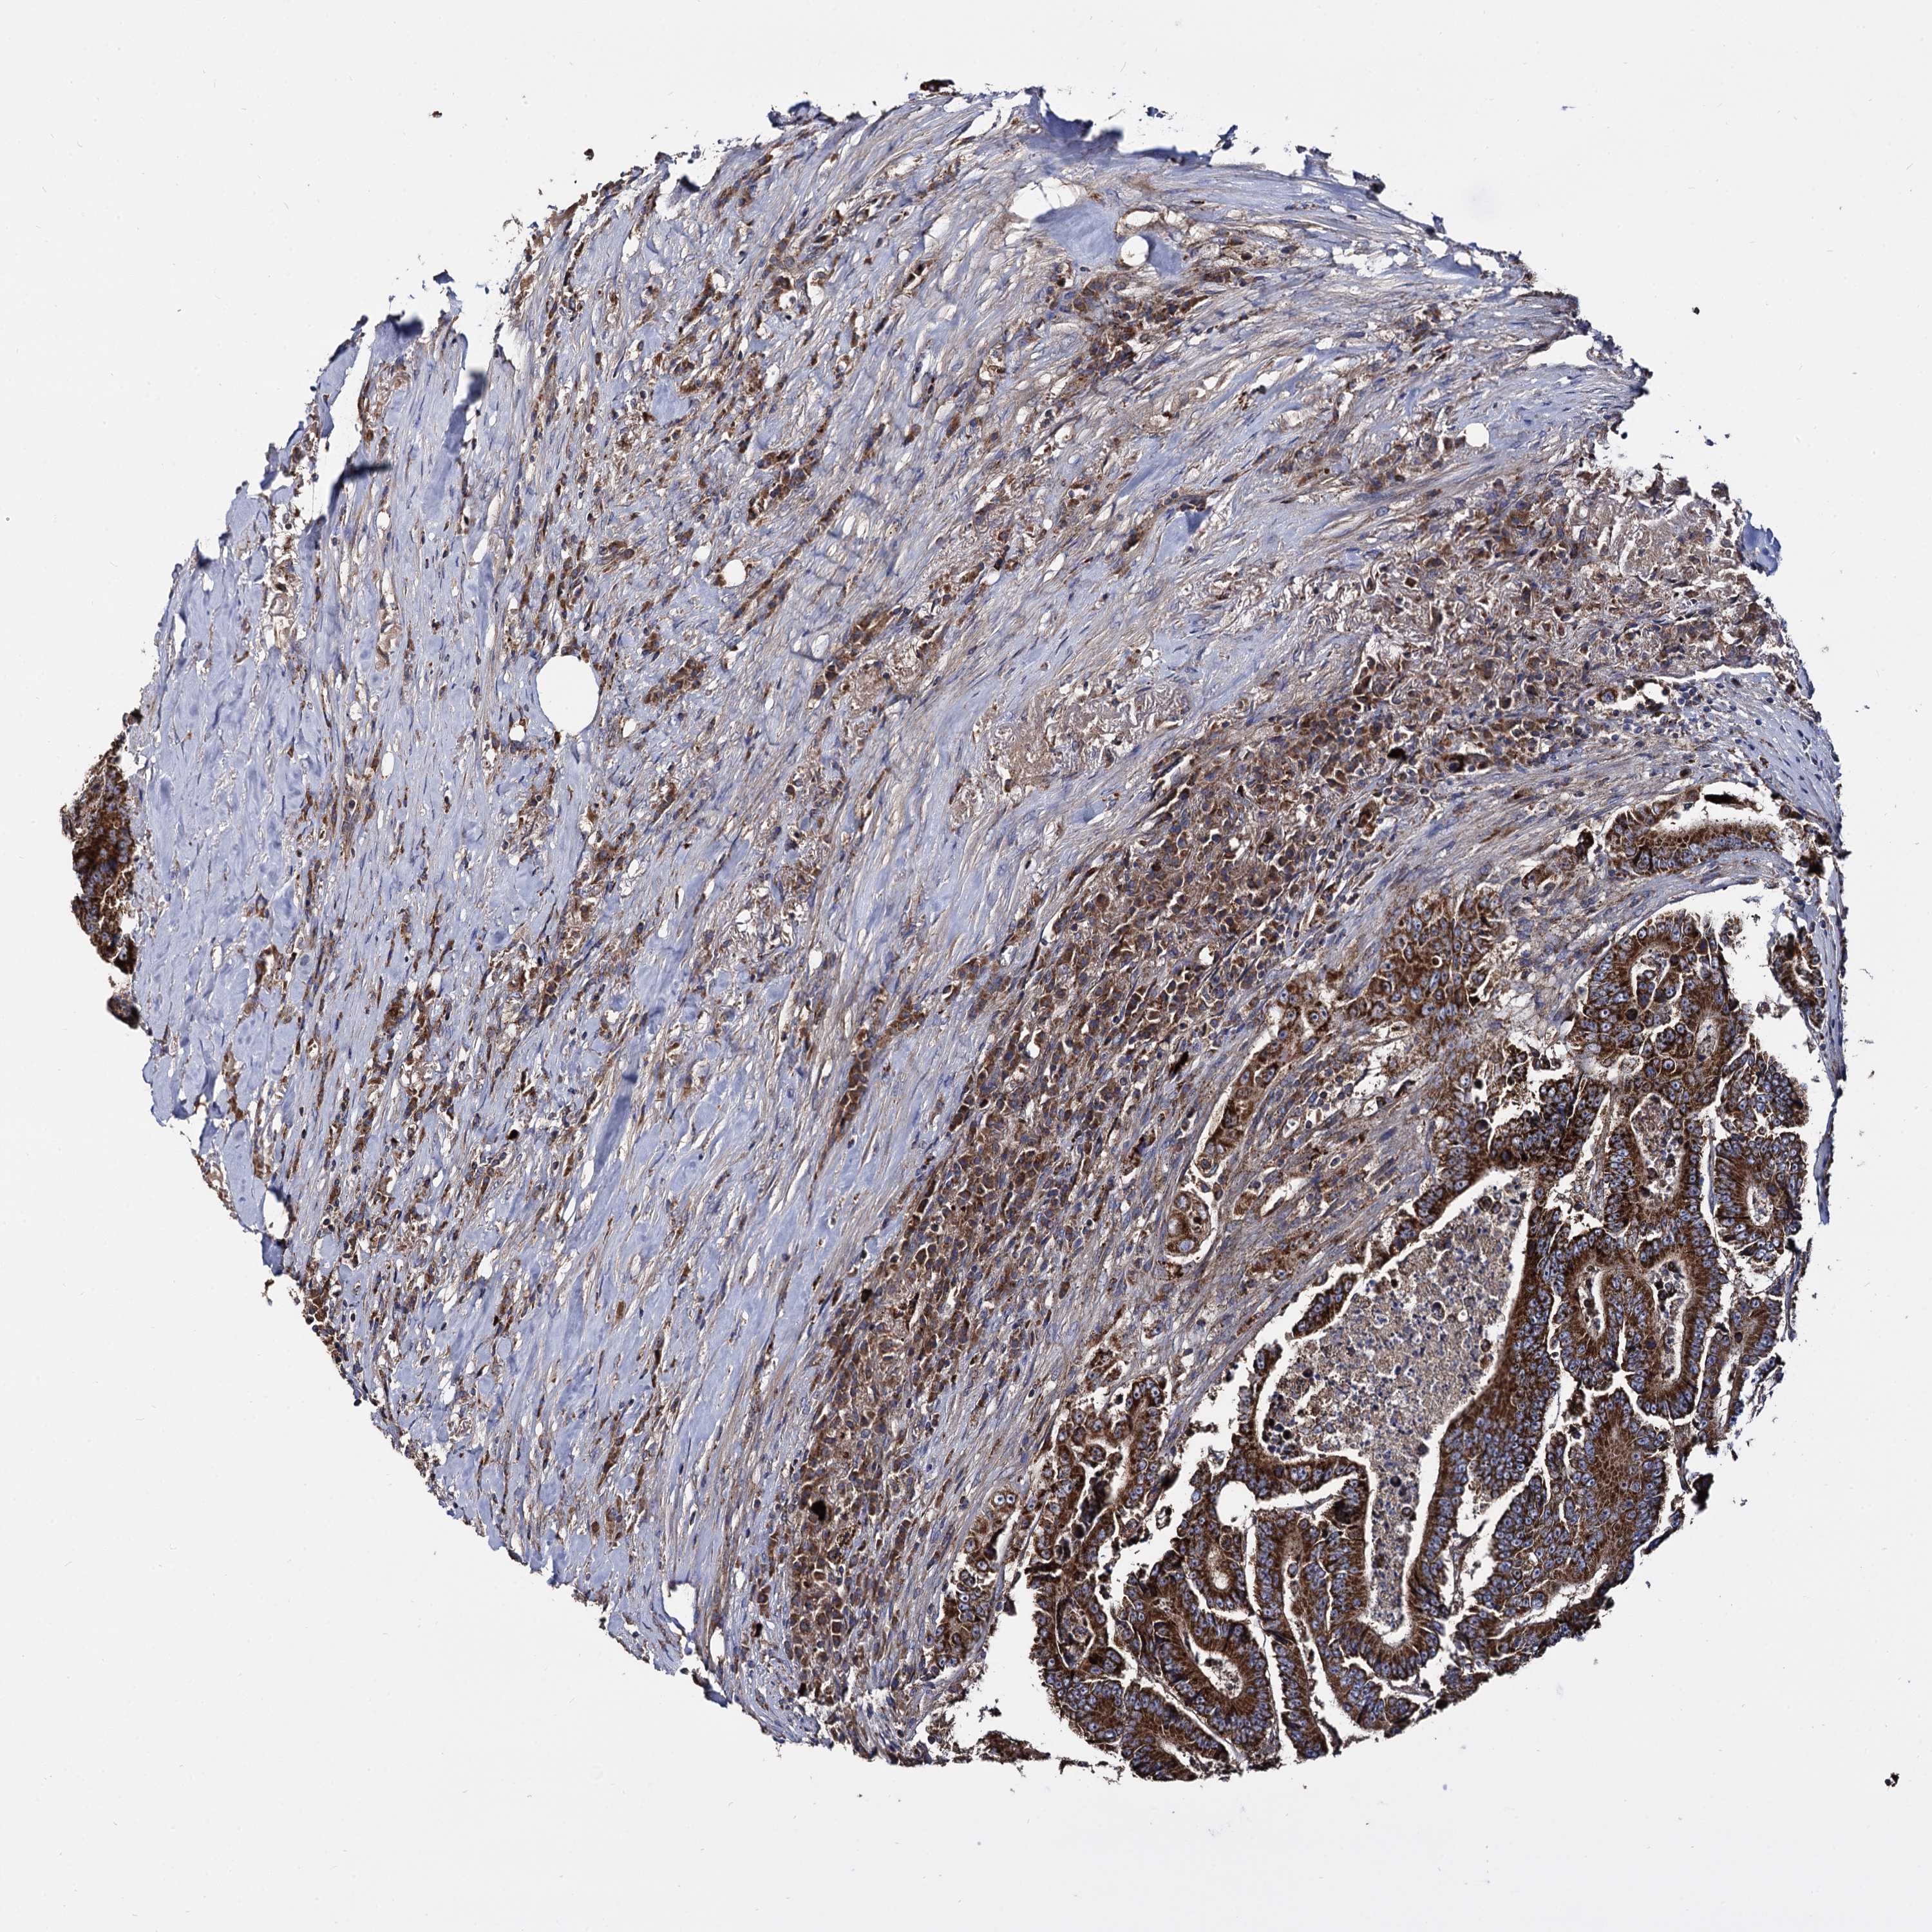

CANCER COLORECTAL CANCER Show tissue menu

Colorectal cancer

Human cancer

Colon adenocarcinoma